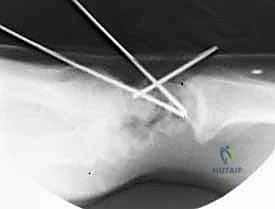

2. دمج المفصل الزورقي المربعي المنحرف (STT Fusion)

تُستخدم هذه التقنية عندما يكون التهاب المفاصل مقتصراً على المفصل بين العظم الزورقي (Scaphoid) والعظم المربعي (Trapezium) والعظم شبه المنحرف (Trapezoid).

* الآلية: يتم دمج هذه العظام الثلاثة فقط.

* النتيجة: يمنع هذا الدمج الانهيار المستقبلي للرسغ ويوفر راحة ممتازة من الألم، مع الحفاظ على حركة واسعة نسبياً. يتطلب هذا الإجراء مهارة عالية لضمان تثبيت العظم الزورقي بالزاوية التشريحية الصحيحة تماماً.